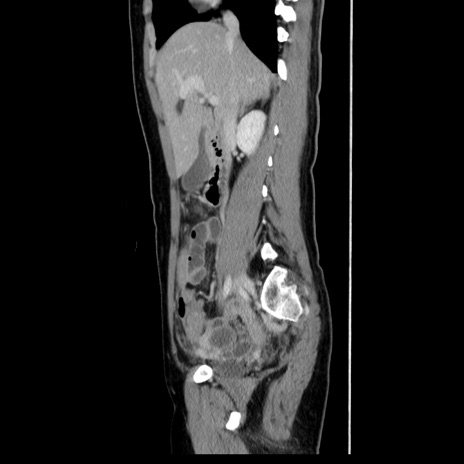

症例39(矢状断像)

【症例】40歳代女性

【主訴】上下腹部痛

【現病歴】2日目から下腹部痛あり。夜間は痛みで眠れなかった。昨日より上腹部痛と下痢が出現。臥位で痛みは軽快したため、休んでいた。本日になって臥位でも立位でも痛みが強くなってきたため救急要請。

【既往歴】子宮内膜症

【身体所見】部:平坦・軟、左上下腹部に圧痛あり、反跳痛あり。

【データ】WBC 21800、CRP 26.78

CT